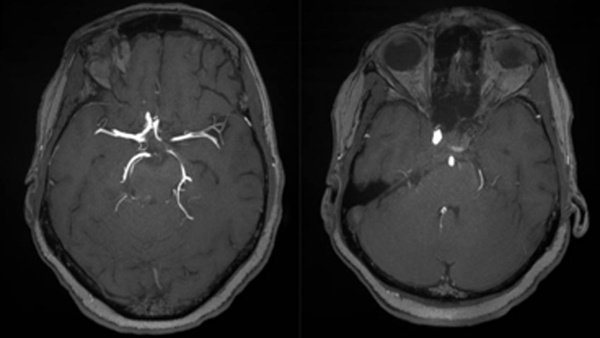

Recanalization of late internal carotid artery occlusion after implantation flow-diverter stent implantation